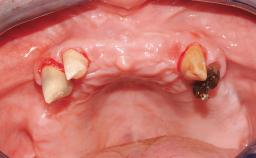

Conventional Loading of Eight Implants in the Maxilla and Final Restoration with a Full-Arch Gold-Ceramic FDP

A 35-year-old Caucasian female presenting with advanced periodontal disease involving both the maxillary and the mandibular dentition was referred for evaluation. The patient, a non-smoker in good general health, requested treatment for recurrent periodontal abscesses, tooth mobility, and discomfort during chewing, as well as restoration of her missing teeth with a fixed prosthesis to improve mastication and esthetics. All residual maxillary teeth exhibited plaque deposits, deep pockets, bleeding on probing, and class III mobility and were evaluated as hopeless. All residual mandibular teeth except tooth 37 could be maintained after periodontal therapy.

Case Type Edentulous Maxilla

Jaw Maxilla

Area Full-Arch